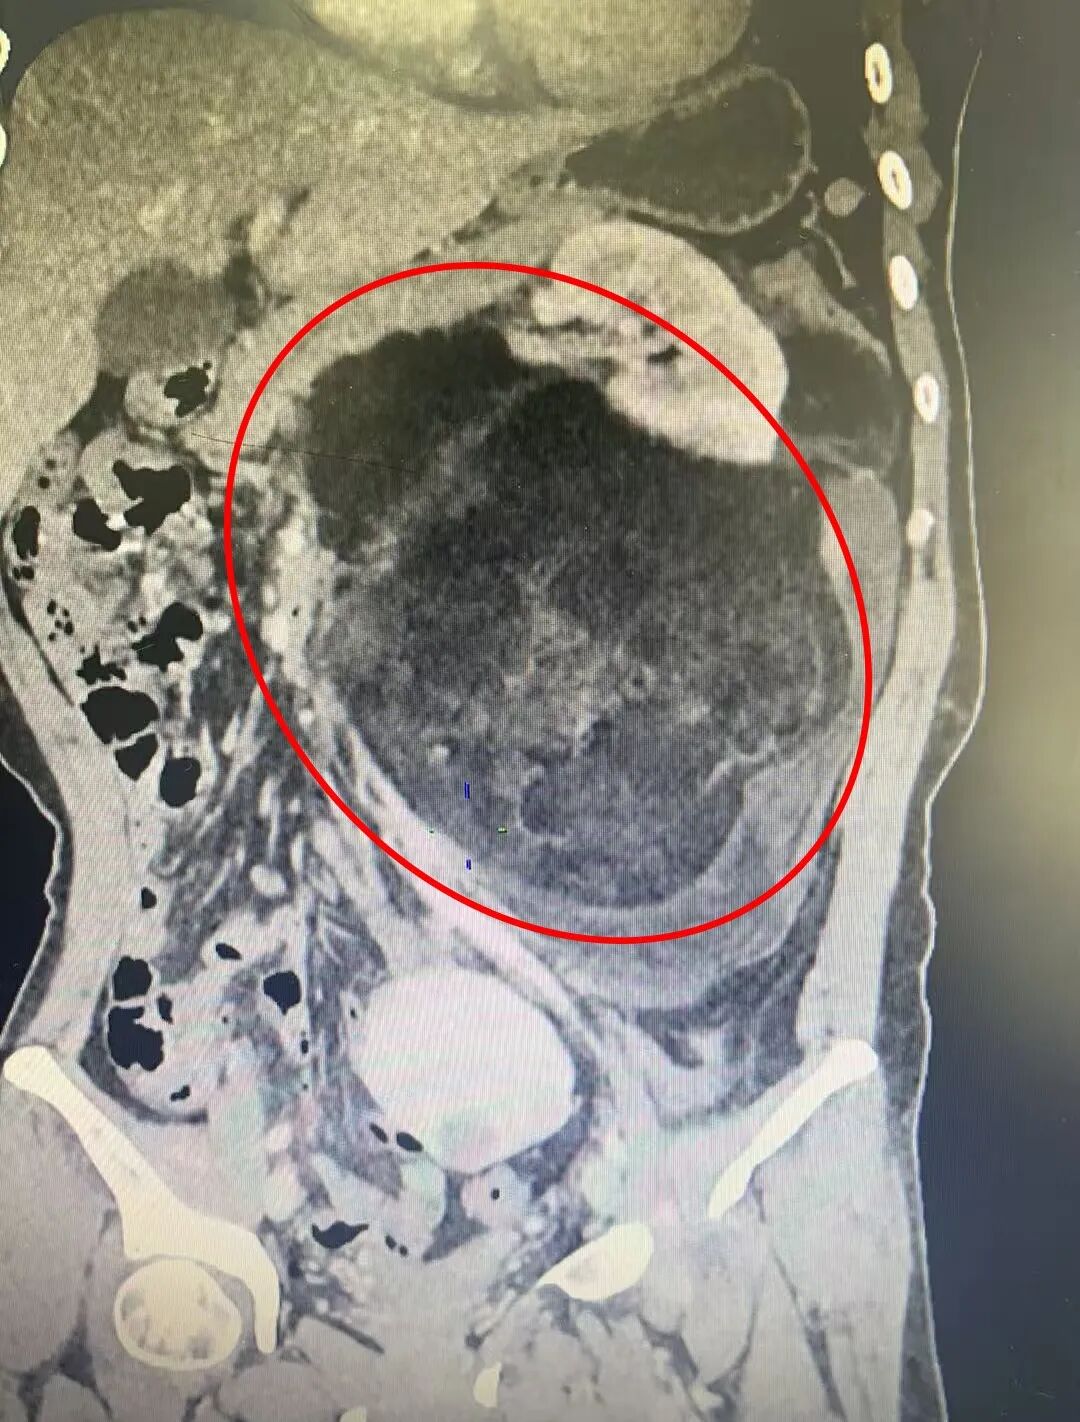

急诊科医生接诊后,病情比较特殊,第一时间向急诊科石聪辉主任汇报并为王女士安排相关重点检查。腹部增强 CT 检查后发现她左腹膜后有一个巨大占位性病变。病情特殊,急诊石聪辉主任立刻启动院前肿瘤多学科会诊机制,泌尿二科、普外科、肿瘤内科、放射科等科室专家共同评估病情,最终高度考虑「左腹膜后巨大肿瘤:脂肪肉瘤可能」,以泌尿外科病情为主,遂收入泌尿二科进一步诊治。

进一步检查确认,王女士的肿瘤长径接近 30 厘米,已越过腹正中线,和周围的胰腺、空肠、左肾、结肠及血管等脏器 紧密粘连,分界不清。如此巨大的肿瘤,不仅手术切除难度极高,还可能在术中损伤周围重要脏器或血管,引发大出血等致命风险。

患者住院完善相关检查后,为确保手术安全,漳州第三医院副院长韩聪祥再次组织普外科、肿瘤内科、放射科、麻醉科、病理科等多学科专家进行术前多学科讨论。专家们反复分析影像学资料,精准评估肿瘤与周围组织的解剖关系,详细探讨手术中可能出现的情况及手术预案,最终制定出「经腹左腹膜后巨大肿瘤切除+左肾切除,备左半结肠切除」的个性化手术方案,同时敲定了详尽的术中应急处置方式,并与患者及家属进行详细的沟通解释,取得配合和理解。